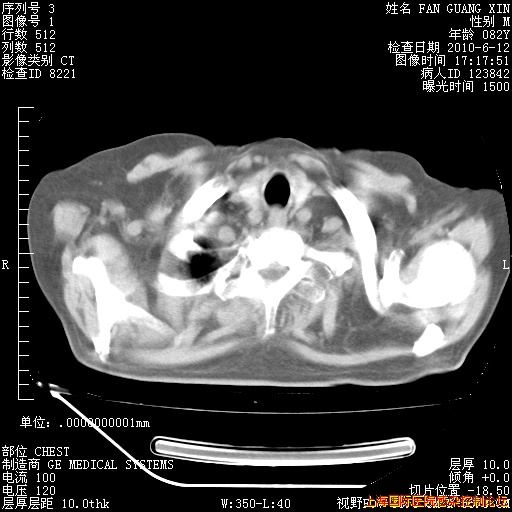

补发6月12日肺部CT肺窗

6月12日肺窗

6月12日纵膈窗